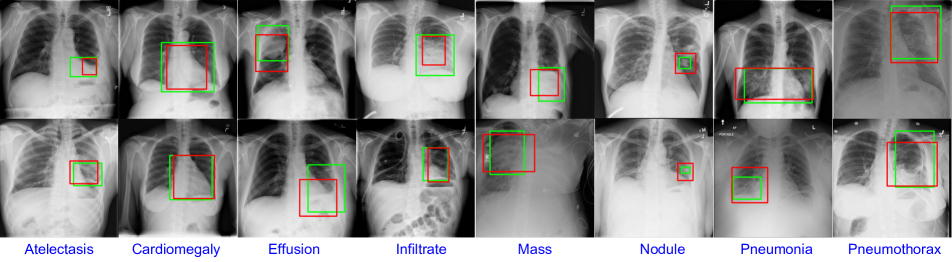

Both quantitative and qualitative visual evaluations show that our proposed model obtains significant improvement over the previous published state-of-the-art results on disease classification and localization. Visual evaluations indicate a strong alignment and correspondence between the clinical annotations and the predicted disease candidate regions shown in figure 1.

Refer to caption

Figure 1: Examples of the disease localizations generated from our network. The localization output from our network (red bounding box), that trained only with image-level annotation, match with the ground truth localization (green bounding box).